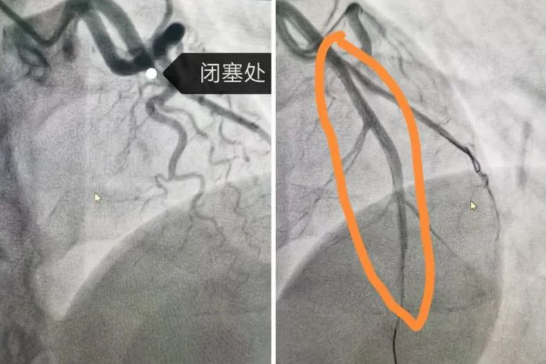

8點30分,導管室迎來了第一批患者,兩個手術間同時啟動。第1手術間接診的是一位31歲的急性心肌梗死男性患者,他因胸痛和呼吸困難被緊急送醫(yī)。冠狀動脈造影顯示,患者的左冠前降支完全閉塞,情況十分危急。在院長隋立有的帶領下,醫(yī)護團隊緊密配合,迅速為患者實施了PCI手術。經(jīng)過緊張而有序的操作,成功開通了閉塞的血管,并植入一枚支架,恢復了血流,改善了心肌供血,挽救了這位年輕患者的生命。